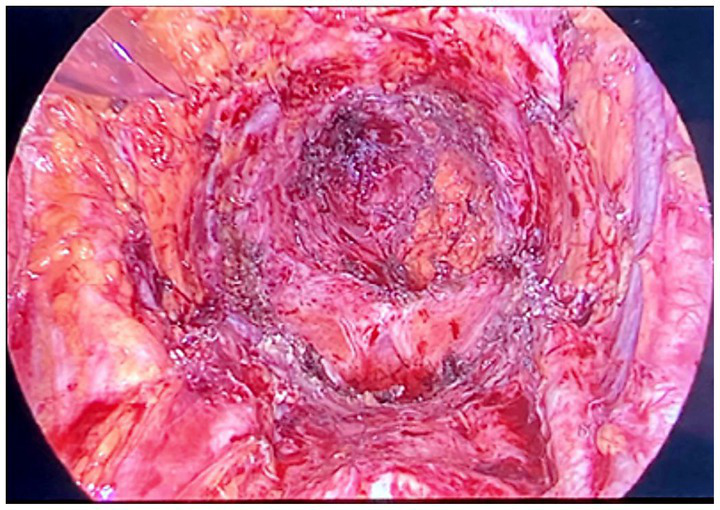

The clinical picture of advanced or relapsing neoplastic disease is associated with an often completely subverted pelvic anatomy, also on account of other previously performed treatments. In these cases, describing and performing a standard procedure is not possible (7), and the operative strategy was modulated based on the highlighted picture and the accessibility of anatomical spaces. An overview and a detailed description of the surgical approach is presented in Supplementary Appendix. Figures 1, 2 show some of the main surgical steps of the laparoscopic surgical approach. Figure 3 presents a laparoscopic view of the empty pelvis at the end of exenteration surgery. All surgical interventions were carefully evaluated, and data on the incidence of intraoperative, postoperative, and long-term complications were collected. Complications were classified and graded according to the Clavien-Dindo classification (15). This classification divides complications into five classes of increasing severity, starting from I, which includes mild complications that do not require specific treatment, to V, which corresponds to the patient’s death. Major complications were defined as grade > III complications. If more than one complication occurred, the complication with the highest degree was included in the analysis. In order to highlight the occurrence of any complications, a daily clinical evaluation was performed postoperatively, and additional tests (e.g., computed tomography with contrast and nuclear magnetic resonance) or exploratory laparoscopy were performed if clinically indicated by the appearance of signs and symptoms (e.g., fever, significant reduction in hemoglobin, bleeding, abdominal pain, bowel obstruction). Routine hematological parameters including leukocyte count (WBC), platelets, lymphocytes, C-reactive protein (CRP), procalcitonin, and fibrinogen were measured. Among these, the blood concentrations of fibrinogen were measured and evaluated daily, and fibrinogen was used as a complication marker to identify any possible inflammation, as described in a work by Macciò et al. (16). In that study, fibrinogen had a higher predictive value for postoperative complications than WBC; in turn, fibrinogen levels were directly related to other inflammation indices such as CRP. After discharge, the patients were instructed to communicate their clinical and health conditions via telephone every 48 h. The patients underwent a clinical evaluation after 1 week and subsequently every 2 weeks (or sooner if symptoms appeared) until progression occurred. Additionally, they were advised to contact the ward if they experienced symptoms attributable to the procedure such as fever, vaginal discharge and/or bleeding, abdominal pain, pelvic discomfort, and constipation. Data regarding possible subsequent hospitalizations, duration of hospitalization, reinterventions, and administered therapies were also analyzed.

Figure 3

Laparoscopic view of the empty pelvis at the end of the exenterative surgery.